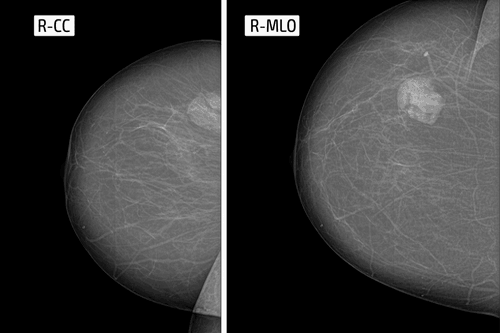

फाइब्रोएडीनोमा की जांच के लिए डॉक्टर सबसे पहले स्तनों की जांच करते हैं। बीमारी की सही जानकारी के लिए ब्रेस्ट अल्ट्रासाउंड भी की जा सकती है। स्तन में गांठ होने पर सूई की मदद से या फिर बायोप्सी की जा सकती है। बायोप्सी या सिरिंज की मदद से गांठ के एक टुकड़े की जांच की जाती है। माइक्रोस्कोप की मदद से गांठ में किस तरह का फाइब्रोएडीनोमा है या कैंसर है। इसकी जानकारी मिल जाती है। जिससे बीमारी कितनी गंभीर है यह आसानी से समझा जाता है। इसके अलवा फाइब्रोएडीनोमा के बारे में जानने के लिए ब्रेस्ट एमआरआई होती है।

अल्ट्रासाउंड

अल्ट्रासाउंड एक प्रक्रिया है, जिसमें हाई एनर्जी वेव्स इंटरनल टिश्यू को बाउंस करती हैं, जिससे इको पैदा होती है। यह गूंज शरीर के टिश्यू की एक तस्वीर बनाती है, जिसे सोनोग्राफ कहते हैं। बाद में, इस चित्र का विश्लेषण किया जाता है।